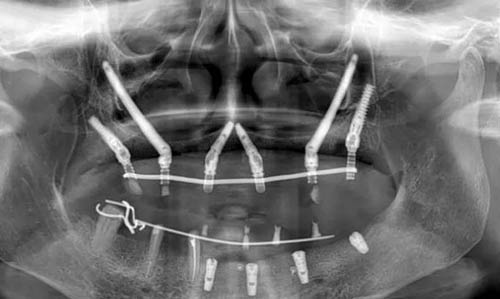

穿颧穿翼种植牙作为一种可靠的牙科手术技术,近年来在口腔医学领域逐渐受到关注。这种技术通过在上颌骨质疏松区域,利用高精度的3D打印导板辅助,将人工牙根直接固定于坚硬的颧骨或翼突区骨骼结构上,为那些因牙槽骨条件不佳而难以进行传统种植牙的患者提供了新的希望。然而,关于穿颧穿翼种植牙的可靠性问题,却一直是患者和医生关注的焦点。

穿颧穿翼种植牙技术的可靠性,首先体现在其显著的生物力学优势上。由于植体更深入骨骼内部,提供了更高的稳定性和支持力,使得种植牙能够长期保持稳固,不易松动或脱落。这一特点对于那些因长期缺牙导致骨量不足的患者来说,尤为重要。此外,穿颧穿翼种植牙手术微创,术后反应轻,患者体验相对舒适,且改善期较短,大大减轻了患者的痛苦和不便。